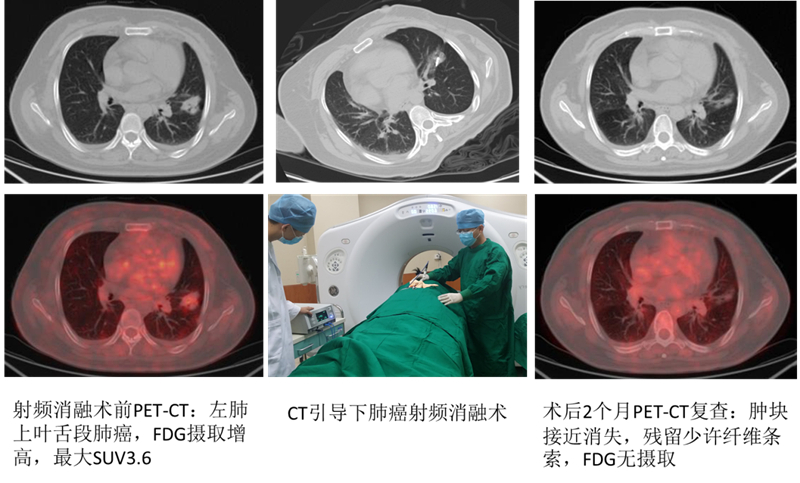

北京清华长庚医院8月27日电(通讯员  董鸿鹏)患者系老年女性,因“腰腿痛半年,加重三个月”于外院拟行腰椎间盘突出症手术治疗。术前胸片发现左肺阴影,胸部CT提示“左肺团片影,慢性炎症可能性大,占位性病变不除外,建议抗炎治疗后复查”。患者于2015年5月初来我院“影像介入门诊”就诊,放射科马永强医师阅片后考虑病变肺癌可能性大,建议穿刺活检明确诊断。征得患者及家属同意后,马永强医师为患者左肺病灶行CT引导下穿刺活检,术后病理提示“浸润性腺癌,外院PET-CT全身扫描提示“左肺上叶舌段占位,FDG摄取增高,最大SUV3.6,同时发现L5棘突骨转移,属肺癌晚期,无手术切除机会。在征得患者及家属同意后,马永强医师于2015年5月中旬为患者行肺癌射频消融术治疗,手术顺利,无并发症发生,患者术后2个月外院PET-CT复查提示:左肺肿块接近消失,仅残留少许纤维条索,FDG无摄取。治疗效果显著,患者及家属送来锦旗表示感谢。